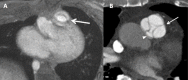

Congenital pulmonary artery anomalies represent a diverse group of abnormalities, ranging from asymptomatic incidental findings to causes of sudden cardiac death. While some may be recognized in childhood, others may be found incidentally in adulthood. We review the clinical and imaging findings in patients with congenital anomalies of the pulmonary arteries, including valvular and perivavular anomalies as well as abnormal narrowing, course and communications of the pulmonary arteries. We also discuss the role of various imaging modalities in the evaluation of these patients. It is vital to be aware of the key radiologic manifestations and associated haemodynamic consequences in these conditions in order to facilitate accurate diagnosis and prognostic stratification.